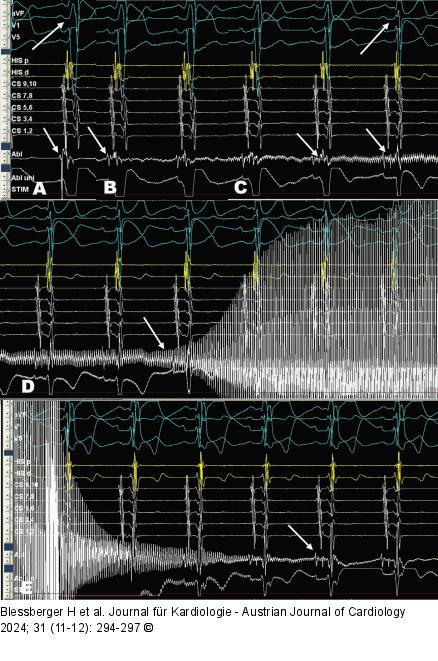

Abbildung 5: Kryo-Ablation Intrakardiale Elektrogramme während der Kryo-Ablation. His-Katheter liegt im rechten Ventrikel, CS-Katheter in CS-Position, Kryo-Tip-Ablationskatheter (Abl) am atrialen Exit der parahisären akzessorischen Leitungsbahn. (A): Unter Ruhebedingungen zeigt sich im Sinusrhythmus ein Fusionspotenzial am Abl mit frühester ventrikulärer Erregung. Im Oberflächen-EKG zeigt sich eine deutliche Präexzitation. (B): Start des Kryo-Mappings mit Artefaktbildung auf der Ableitung des Abls (Pfeil). (C): Während des Kryo-Mappings Verlust der Präexzitation im Oberflächen-EKG mit Auftauchen des His-Signals am Abl (Pfeile). (D): Nun Start der Kryo-Ablation nach 40 Sekunden (Pfeil). (E): Nach Beendigung der vierminütigen Kryo-Ablation zeigt sich am Abl ein großes, klassisches His-Signal. |

Intrakardiale Elektrogramme während der Kryo-Ablation. His-Katheter liegt im rechten Ventrikel, CS-Katheter in CS-Position, Kryo-Tip-Ablationskatheter (Abl) am atrialen Exit der parahisären akzessorischen Leitungsbahn. (A): Unter Ruhebedingungen zeigt sich im Sinusrhythmus ein Fusionspotenzial am Abl mit frühester ventrikulärer Erregung. Im Oberflächen-EKG zeigt sich eine deutliche Präexzitation. (B): Start des Kryo-Mappings mit Artefaktbildung auf der Ableitung des Abls (Pfeil). (C): Während des Kryo-Mappings Verlust der Präexzitation im Oberflächen-EKG mit Auftauchen des His-Signals am Abl (Pfeile). (D): Nun Start der Kryo-Ablation nach 40 Sekunden (Pfeil). (E): Nach Beendigung der vierminütigen Kryo-Ablation zeigt sich am Abl ein großes, klassisches His-Signal. |